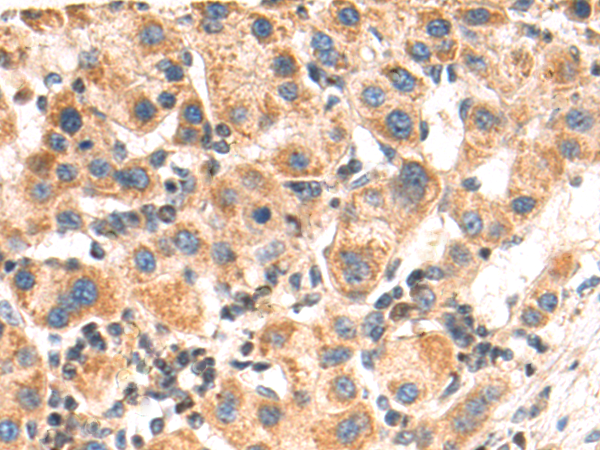

分类: 科研抗体货号: P06915别名: MATE1应用: WB,IHC反应种属: Human